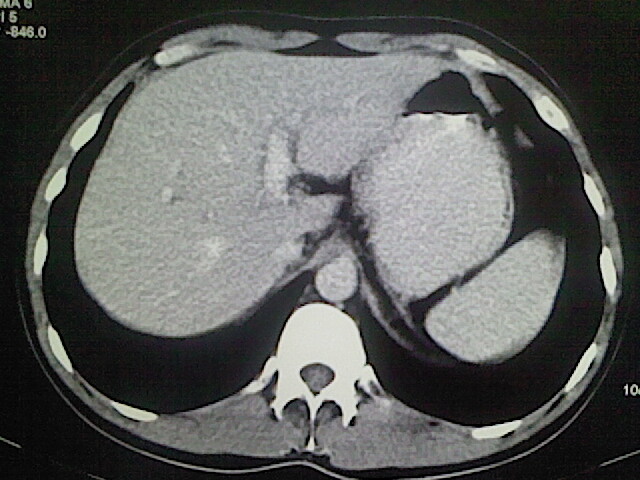

以下是引用卜一在2009-3-14 9:49:00的发言:[br]胆囊萎缩,胆囊壁不规则增厚,内部结构模糊,增强明显强化。另:肝左叶外侧段肝囊肿。支持:慢性胆囊炎!高度可疑:胆囊癌!

以下是引用余辉在2009-3-14 8:48:00的发言:[br]1)慢性胆囊炎。2)肝左叶外侧段肝囊肿。3)脂肪肝。[br]支持,胆囊萎缩,密度增高,不知b超具体有何提示,钙胆汁?结石?

以下是引用jiangjing在2009-3-14 10:18:00的发言:[br]1)慢性胆囊炎。2)肝左叶外侧段肝囊肿。3)脂肪肝。4.】建议行肝功能检查